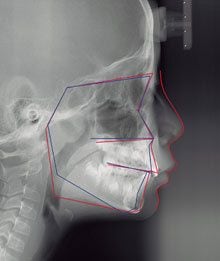

「矯正治療には、正確な診断と治療計画が必要です。特に顔の側面から撮影したセファログラム(写真)の画像がなければ、正確な診断も治療計画を立てることもできません。セファログラムも撮らずに、すぐ矯正治療に入ろうとする歯科医は要注意です」